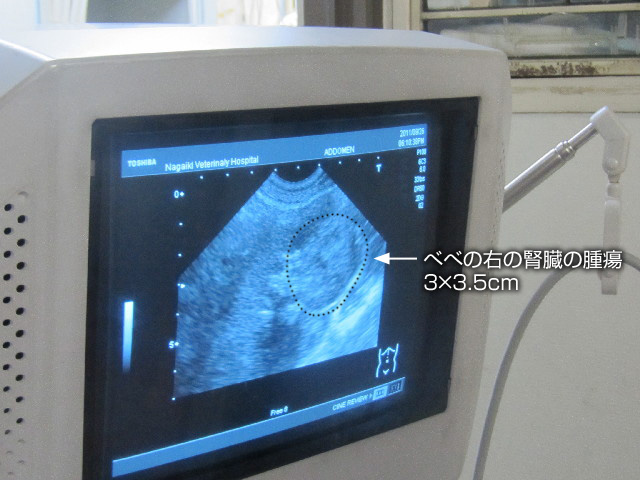

....そうしたら、思いもよらないものがみつかりました(--〆)

右の腎臓に3×3.5cmもある腫瘍が。

3×3.5cmというと、腎臓の25%を占める大きさでかなり大きいらしいです。

↓画像の黒い破線の少し内側が腫瘍。

先生の指先のあたりの、胃の形のような物が腫瘍です。